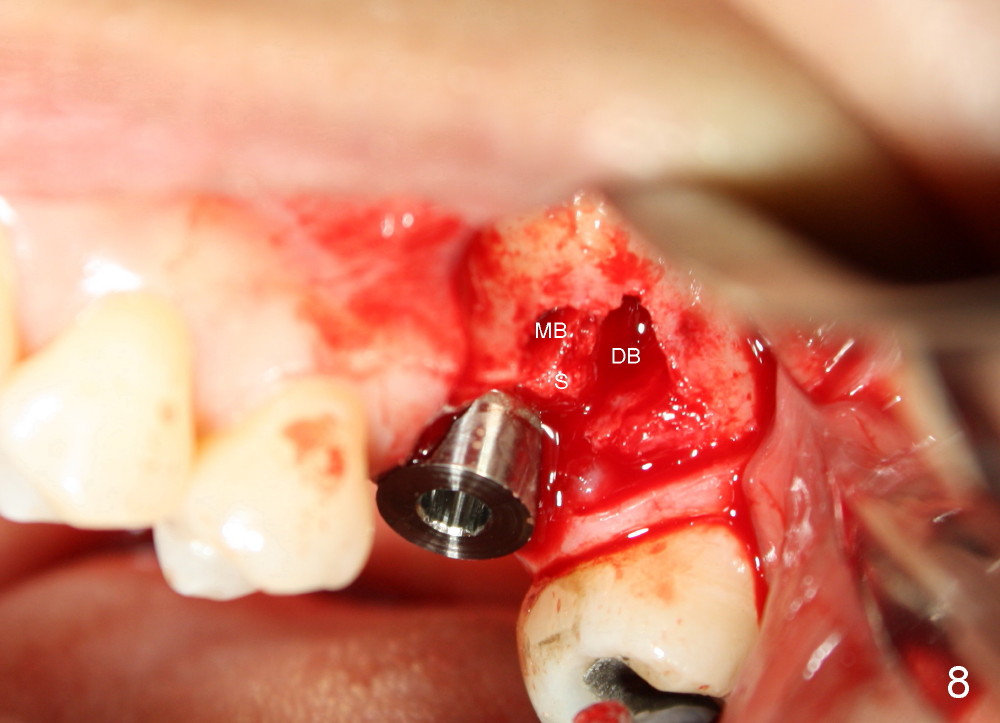

让我们再举例说明证明上颌窦中有骨质:三个月前,四十来岁女士来诊所诊治,左上六不适(图六),咬合面有一个大块银汞充填,周围有裂纹,去除银汞充填后,裂纹延伸至髓腔顶(图七),好像不到髓底,所以尝试根管治疗,但是疼痛没有消失,我们临时决定拔牙立即植牙,但是当时没有足够时间注意上颌窦底板,两眼直盯鄂侧根尖(图六:P),因此最后植牙就植入那么深(图九:I),晚上欣赏自己“杰作”时,才发现上颌窦底板(箭头),虚汗一身:一大节植牙捅进上颌窦,马上打电话给病人,她有些鼻血,但是她还不愿意回来复诊。拔牙后准备在中隔正中植牙,使用骨凿,tap形成植牙窝,后者颊侧骨壁有小面积穿孔,但是上颌窦膜还完整,最后植牙掉入鄂侧牙槽窝(图八;S:中隔;MB:近中颊侧牙槽窝;DB:远中颊侧牙槽窝),植牙很牢,torque>60Ncm。